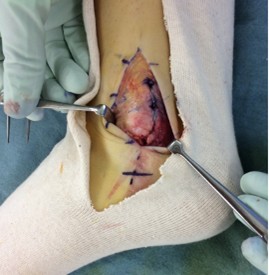

腓骨筋腱脱臼

術中写真